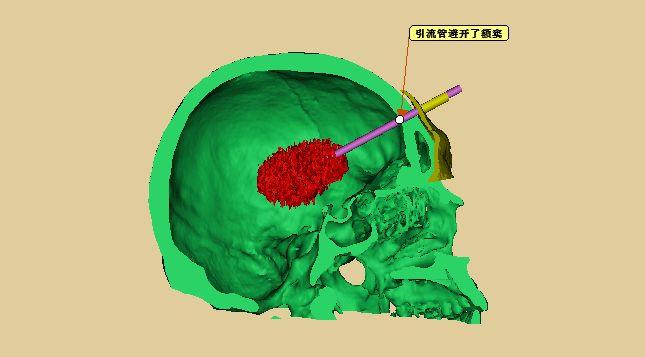

术前模拟设计,引流管位于血肿中心

术前模拟引流管经头部软组织、脑组织后穿刺进入血肿

设计模拟引流管避开额窦

模拟引流管在导板引导下穿刺血肿

重建脑组织并透视化显示引流管穿刺血肿

引流管与血肿、面部的导板关系

设计待打印的面部穿刺导板(黄色部分)

待打印出的模拟穿刺导板、引流管及血肿